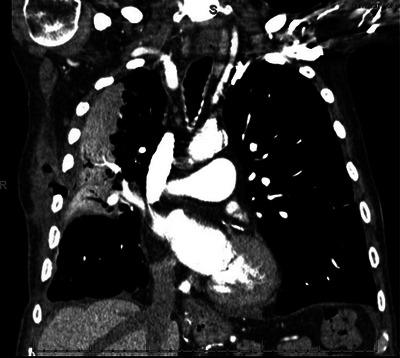

A 76-year-old man with a productive cough.

A 56-Year-Old Man With Chronic Cough, Hemoptysis, and a Left Lower Lobe Infiltrate.

A 74-Year-Old Man Presenting With Cough, Malaise, and Mediastinal Lymphadenopathy.